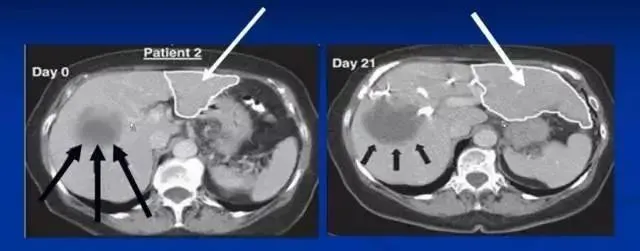

肝硬化是一種由慢性肝臟損傷引起的嚴重疾病,其特征是肝組織纖維化、肝小葉結構破壞和肝功能衰退,可能導致肝功能失代償、肝癌及其他嚴重并發(fā)癥。干細胞治療肝硬化是一種新興的治療方法,近年來(lái)在臨床研究中顯示出顯著(zhù)的潛力和效果。

沈陽(yáng)軍區總醫院消化內科郭曉鐘等經(jīng)股動(dòng)脈肝內自體骨髓干細胞移植治療肝硬化102例報告。

術(shù)后復查提示:

血漿蛋白改善在各項指標中最顯著(zhù),其次為凝血功能的改善,可改善肝臟合成蛋白功能,對目前肝硬化腹水的患者具有積極意義。

第2個(gè)明顯改善的指標為纖維蛋白原和凝血酶原時(shí)間,同樣代表肝臟的合成功能提高。